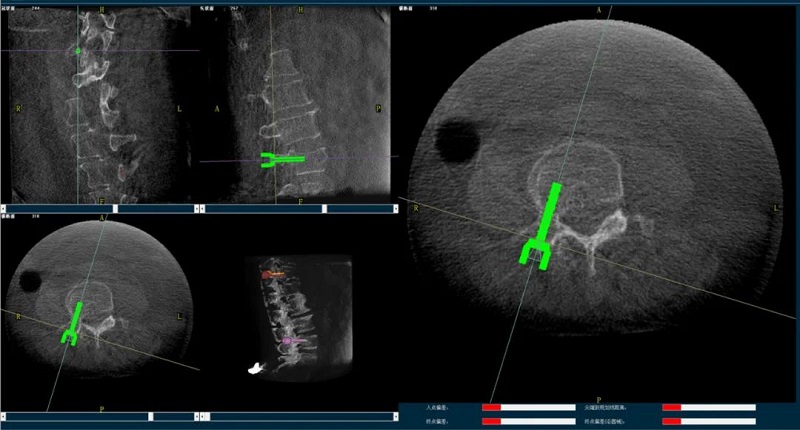

手术机器人规划图像

普爱骨科机器人辅助下的骨科手术